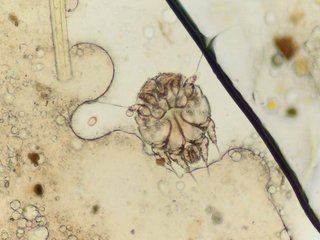

Senza volere strumentalizzare con indicazioni di questa o quella struttura questa è la situazione nella Provincia di Parma e temiamo non solo qui. È ormai da parecchio tempo che ci giungono notizie di strutture per anziani (pubbliche e private) in cui gli ospiti sono colpiti dalla scabbia. Una malattia che storicamente, per sua natura, colpisce persone in condizione di scarsa igiene e poca assistenza sanitaria.

Questo succede, come denunciamo da tempo, perché l'Accreditamento Regionale, per problemi di costi di gestione, lesina in misura inaccettabile l'assegnazione del personale con definizione dei tempi di cura assolutamente limitati e quindi inadeguati. E questo riguarda l'igiene di persone che sono quasi totalmente non autosufficienti per malattie croniche degenerative. Anche la cura sanitaria, proprio perché rivolta a persone non autosufficienti, è del tutto saltuaria, inadeguata per tempo e qualità del servizio garantito.

La cronica e risaputa carenza di personale infermieristico e di operatori sociosanitari rende la qualità dell’assistenza estremamente scarsa con pesanti ricadute sul livello di cura, si riscontrano malattie infettive, compreso casi di scabbia, la cui gestione è assolutamente approssimativa.

Teniamo a precisare che, oltre gli anziani, la scabbia ha colpito anche gli operatori, situazione di cui anche gli organi dell’AUSL di Parma sono a conoscenza.

Manca spesso tutto, l’inadeguatezza e arretratezza degli spazi, l’impossibilità di adottare azioni efficaci d’isolamento soprattutto nei confronti degli anziani affetti dall’Alzheimer, dimostrazione che i casi il cui rischio di diffusione è elevato, come la scabbia, debbano essere trattati direttamente dal Sistema Sanitario attraverso il ricovero presso reparti di malattie infettive, in ambienti e condizioni adeguate.